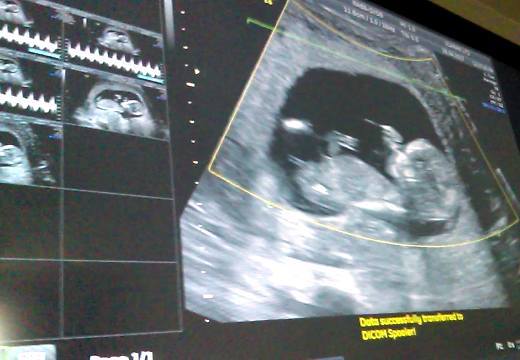

This is the early potty shot my tech gave me at 12+6. I cant make it out. She did give me an educated guess but im wondering if you clever lot agree.Attachment 36019

That looks girly to me, but not as great a shot as I like and also earlier gestation than I prefer to guess at. Good luck.

The nub view looks girly. Do you have more shots of it?

Did you hoped for a 7. Boy ;) i dont think your hope will come true ;) Looks very girly

Looks like a girl to me!